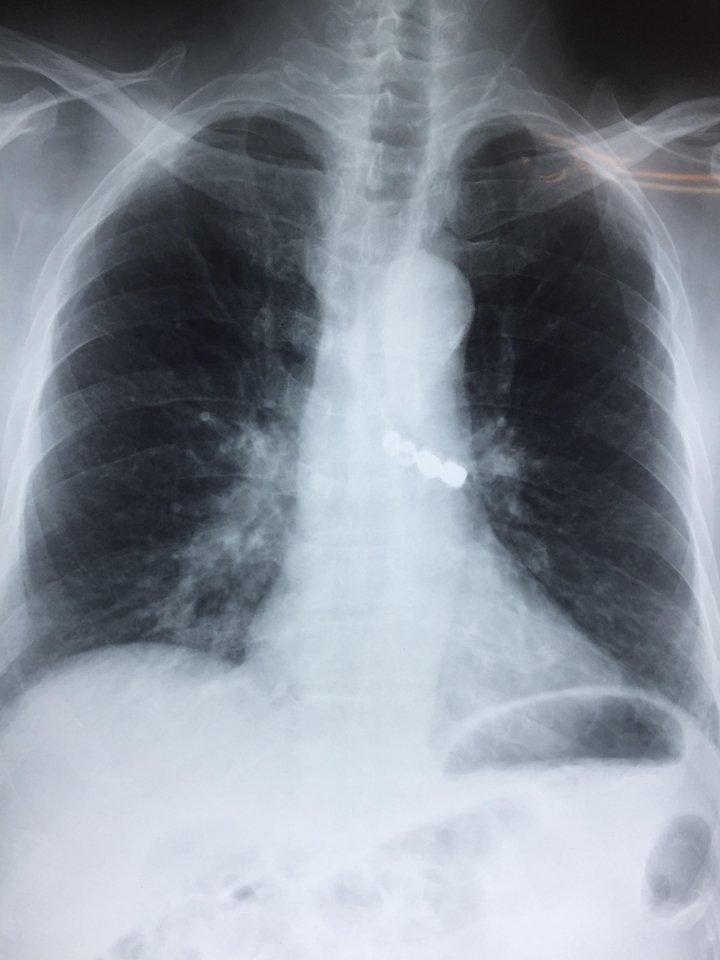

Người bệnh đã được nội soi dạ dày tại Bệnh viện đa khoa tỉnh Thái Bình để tìm dị vật nhưng không thấy; được chụp phim X-quang phổi và phát hiện ra dị vật trong đường thở. Do vượt quá khả năng can thiệp nên người bệnh được chuyển cấp cứu lên Bệnh viện Phổi Trung ương.

| Phim X Quang chụp dị vật bị mắc tại đường thở. (Nguồn: BV Phổi Trung ương) |

Người bệnh được nhập viện vào lúc 11h45 ngày 23/9 trong tình trạng ho nhiều, khó thở. Các bác sĩ của Bệnh viện Phổi Trung ương đã khẩn trương tiến hành hội chẩn và quyết định nội soi phế quản cấp cứu để gắp dị vật khí quản, giải phóng tắc nghẽn đường thở, nhằm cứu sống người bệnh.

Người bệnh đã nhanh chóng được gắp thành công dị vật ra khỏi phế quản, giải phóng đường thở. Dị vật này là 1 cầu răng sứ 4 răng hàm dài 3,5cm đã bị rơi vào khí phế quản trong quá trình lắp răng giả cho người bệnh.